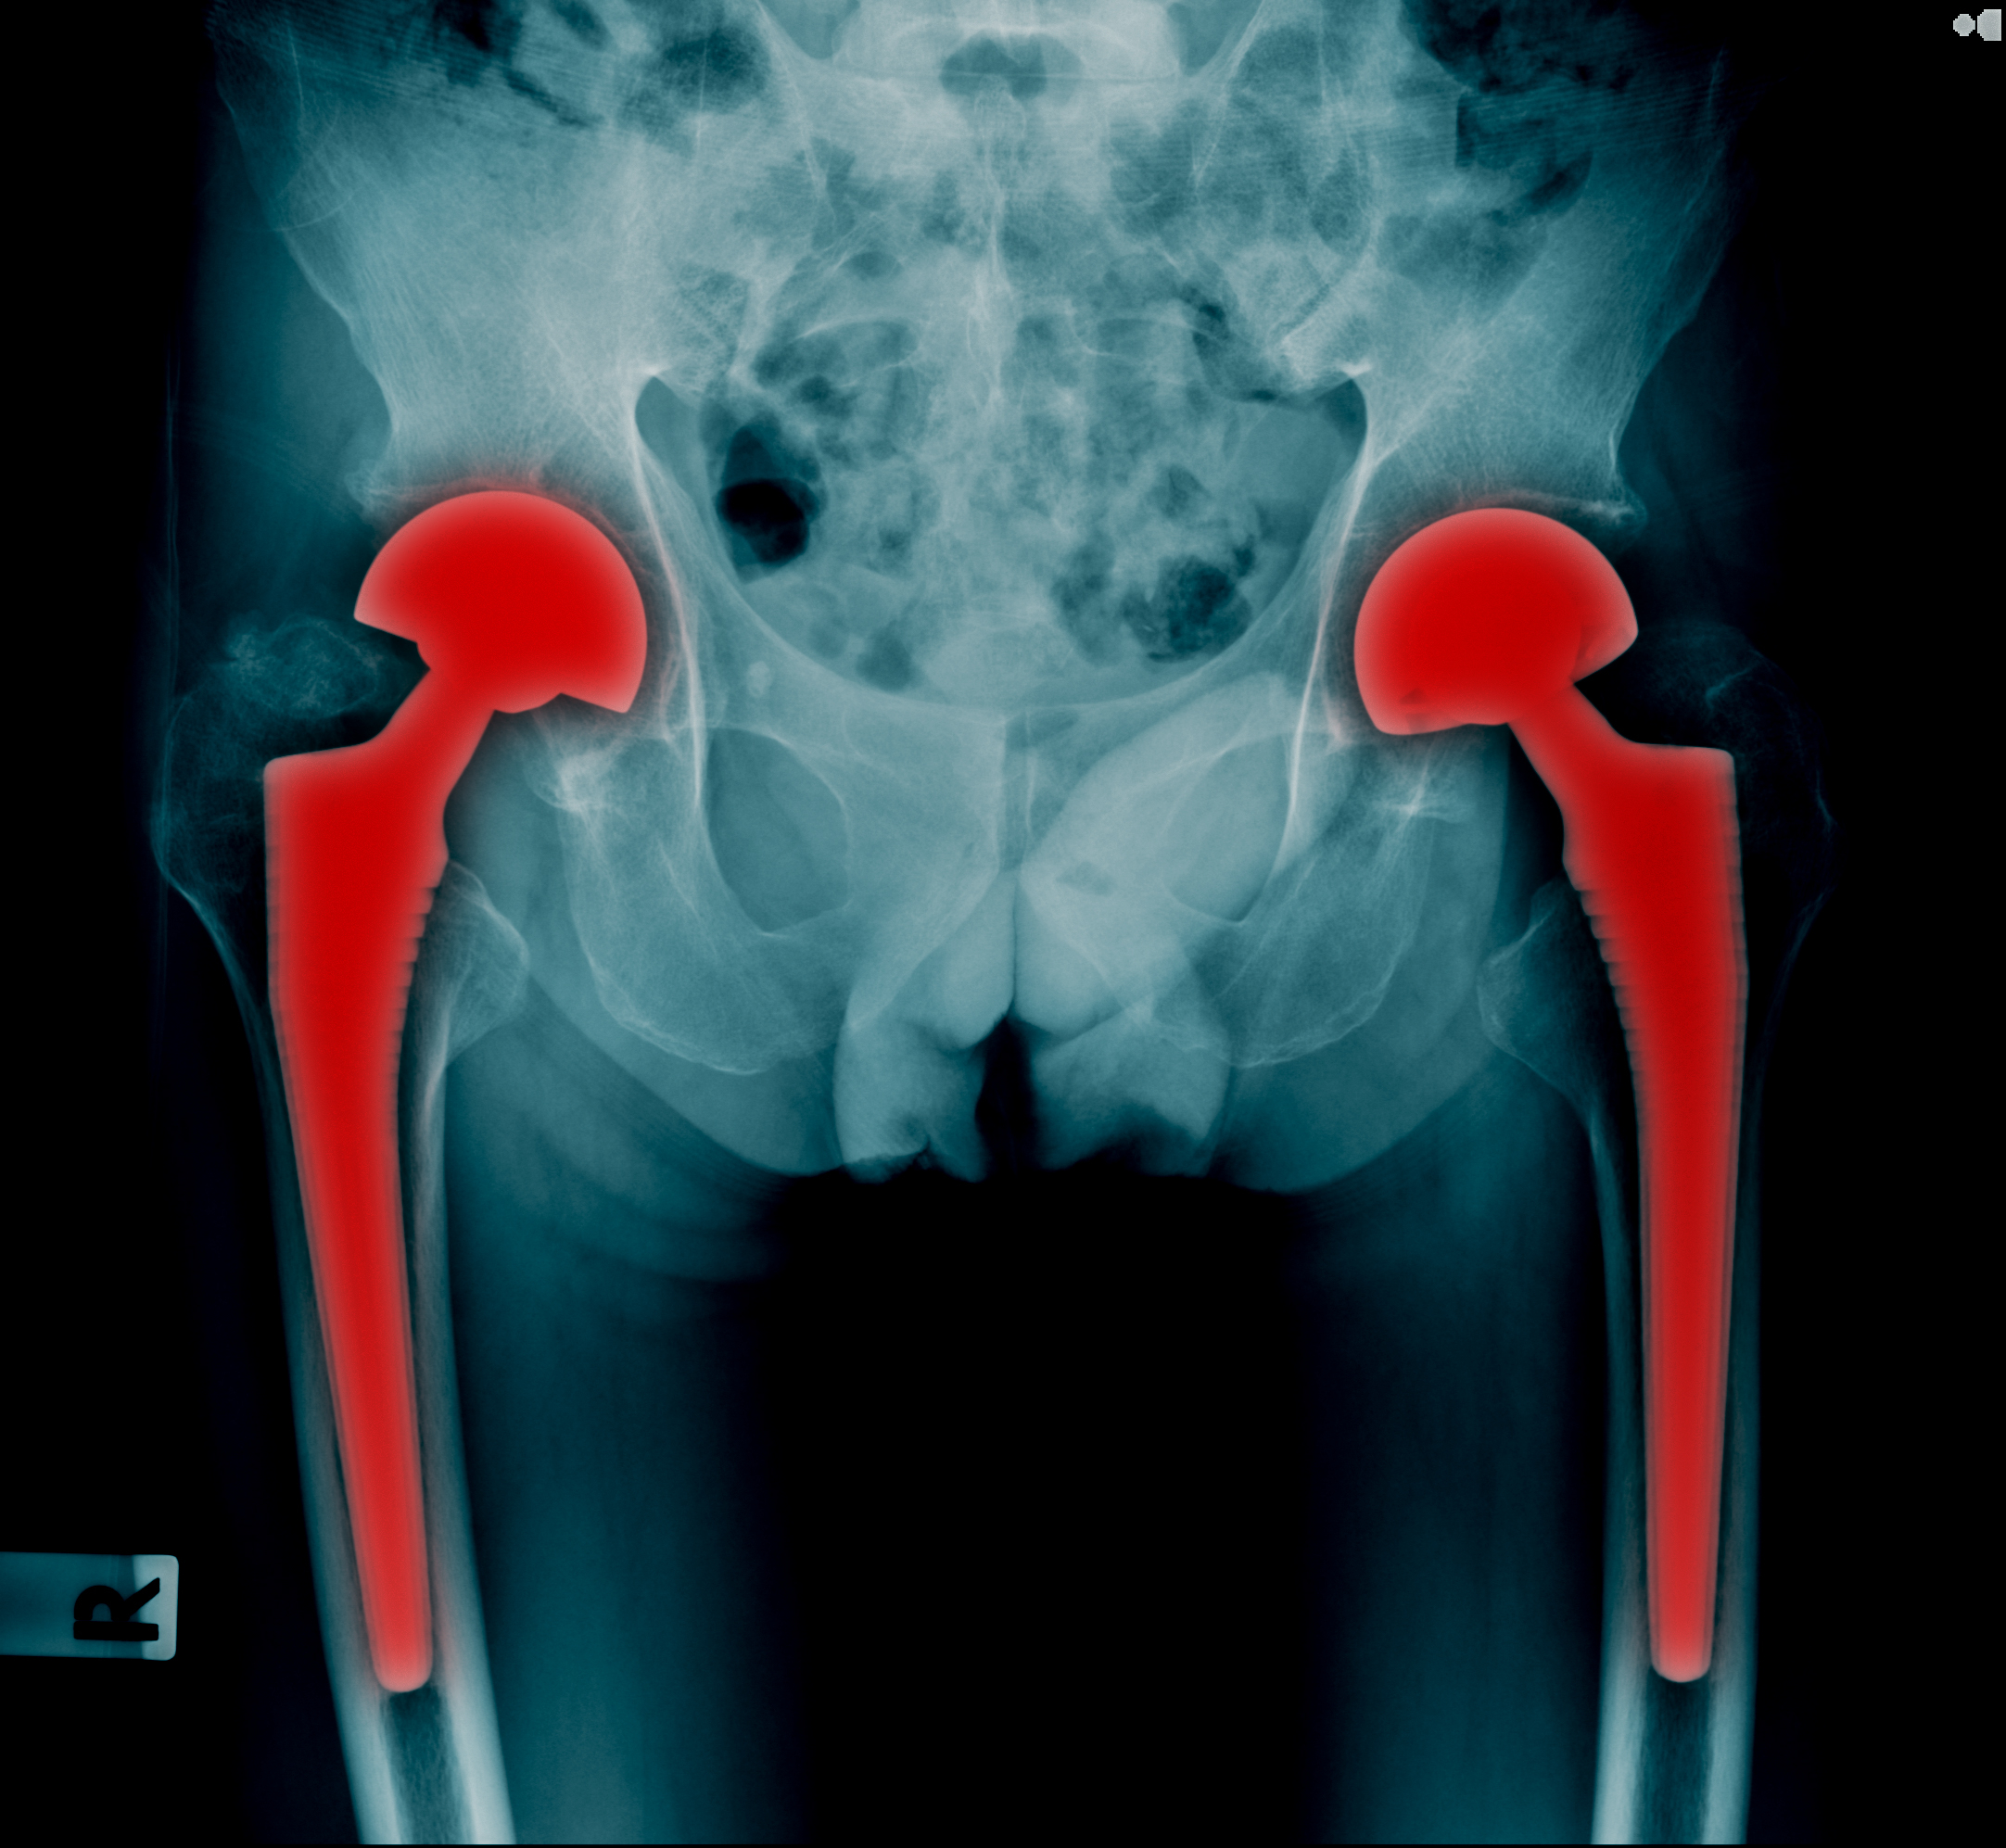

When a Routine Hip Replacement Goes Wrong: Legal and Medical Insights into Sciatic Nerve Injury

This matter involves an adult patient who underwent hip replacement surgery that was complicated by a sciatic nerve injury, resulting in significant functional impairment, including loss of use of the leg and foot drop. These outcomes are not minor or transient; they fundamentally alter mobility, independence, and quality of life. For counsel assessing liability, causation, and damages, the timing and specifics of the surgical procedure are central to the analysis.

Hip replacement surgery may be common, but catastrophic complications like sciatic nerve injury are anything but routine. When such injuries occur, attorneys must look beyond surface-level explanations and examine surgical approach, patient-specific risk factors, intraoperative technique, and postoperative findings.